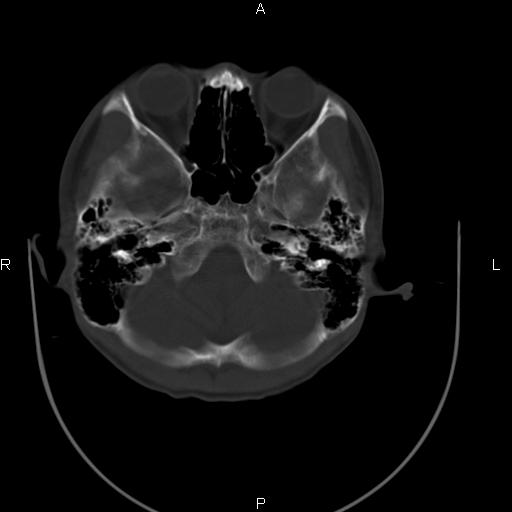

标题: CT27115:大家看一看,这孩子的颅骨表现? [打印本页]

标题: CT27115:大家看一看,这孩子的颅骨表现?

两名中学生打架,脑质内未见异常,未上传。

两例——颅骨结构正常,未见明显骨折征象。

感觉第2个颅缝密度高,额顶部板障有点厚,正常变异?地中海贫血?